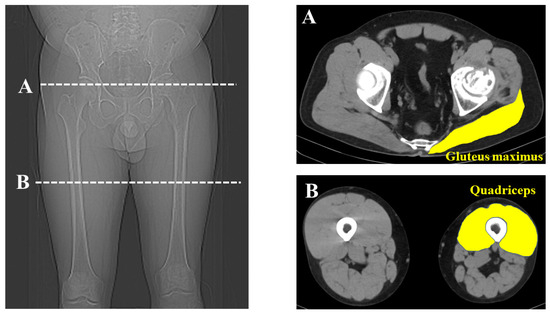

CT was performed from the range of the anterior superior iliac spine (ASIS) to the knee joint (Siemens, Germany; 120 kV, slice thickness; 0.6 mm, 0.5–1 s scan time). The anterior pelvic plane was defined using landmarks of the bilateral ASIS plane and pubic tubercles [17]. The cross-sectional area (CSA) of the gluteus maximus of the affected side was measured at the most proximal point of the affected greater trochanter. The CSA of the affected quadriceps was measured at the middle of the affected thigh. Considering each participant’s physique, the measured muscle volume was normalized for each patient’s body weight (mm2/kg). Each muscle was measured by manual tracing and HUs were derived using imaging analysis software DICOM (syngo.via version VB60) in a 512 × 512 pixel format (Figure 2). Two observers separately measured each muscle twice and the average value was used for evaluation.

Figure 2. Measurement of muscle volume and Hounsfield Units. Cross-sectional measurement of the gluteal maximus and quadriceps was performed using computed tomography images at the greater trochanter (A) and the middle of the thigh (B).